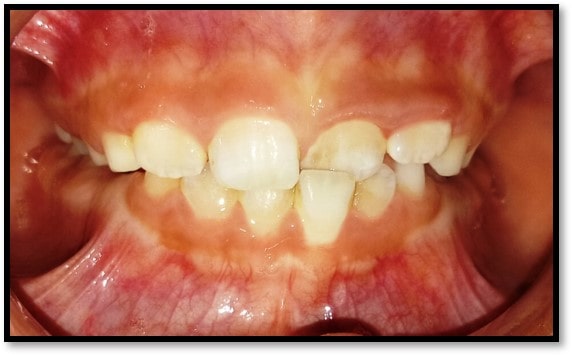

We at the Department of Pediatric & Preventive Dentistry focus on comprehensive oral health care needs of a child from infancy to adulthood and provide comprehensive, therapeutic as well as preventive care to all children including those with special care needs.

- Proposed a modification of Angle’s classification for application in primary dentition and various cross sectional studies have been carried out to validate its application.

Treatment and Services